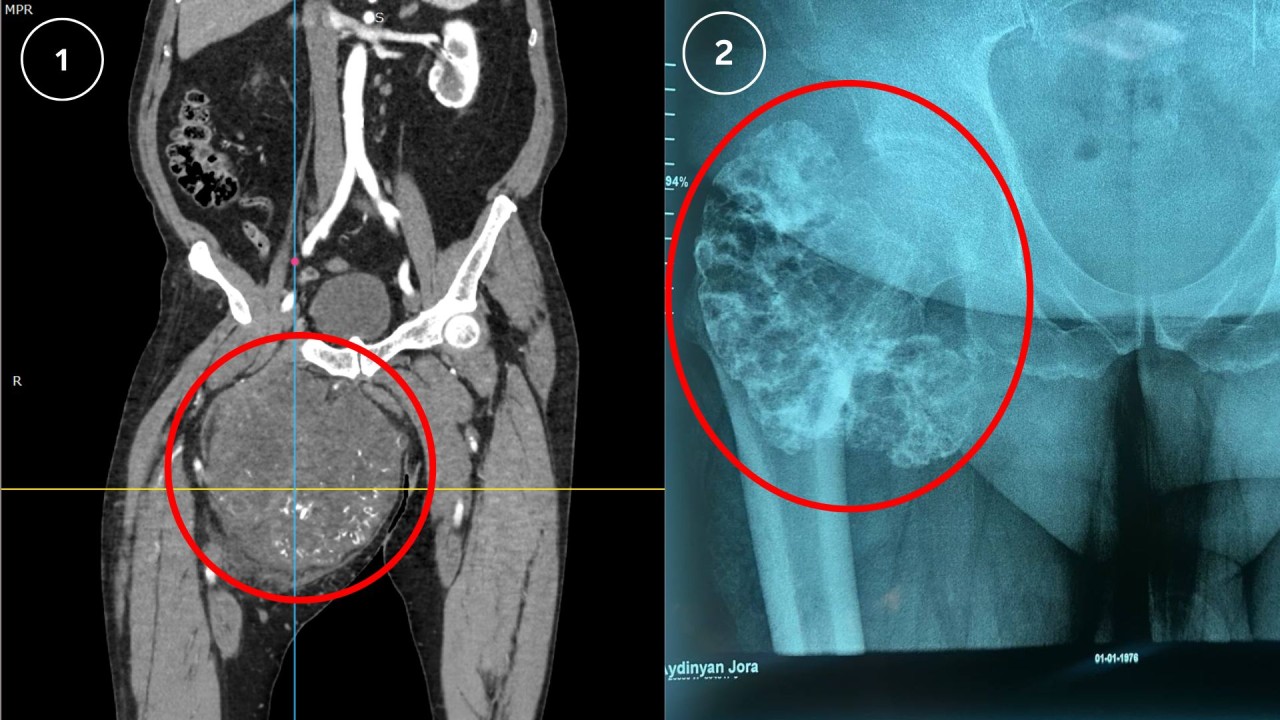

Կլինիկական բացառիկ դեպք. որովայնի խոռոչի հսկա մետաստատիկ ուռուցքը ամբողջությամբ հեռացվել է

ՈւԱԿ Որովայնային և էնդովիրաբուժության բաժանմունք է դիմել 1951թ. ծնված տղամարդ՝ գանգատվելով որովայնի շրջանում բութ ցավերից, որովայնի չափերի զգալի մեծացումից և ընդհանուր արտահայտված թուլությունից։Պացիենտը նախկինում՝ 2022 և 2024 թվականներին, ենթարկվել է վիրահատական միջամտությունների ձախ ստորանրակային շրջանի գոյացության կապակցությամբ, որի հյուսվածաբանական քննությամբ ախտորոշվել էր

ՈւԱԿ Որովայնային և էնդովիրաբուժության բաժանմունք է դիմել 1951թ. ծնված տղամարդ՝ գանգատվելով որովայնի շրջանում բութ ցավերից, որովայնի չափերի զգալի մեծացումից և ընդհանուր արտահայտված